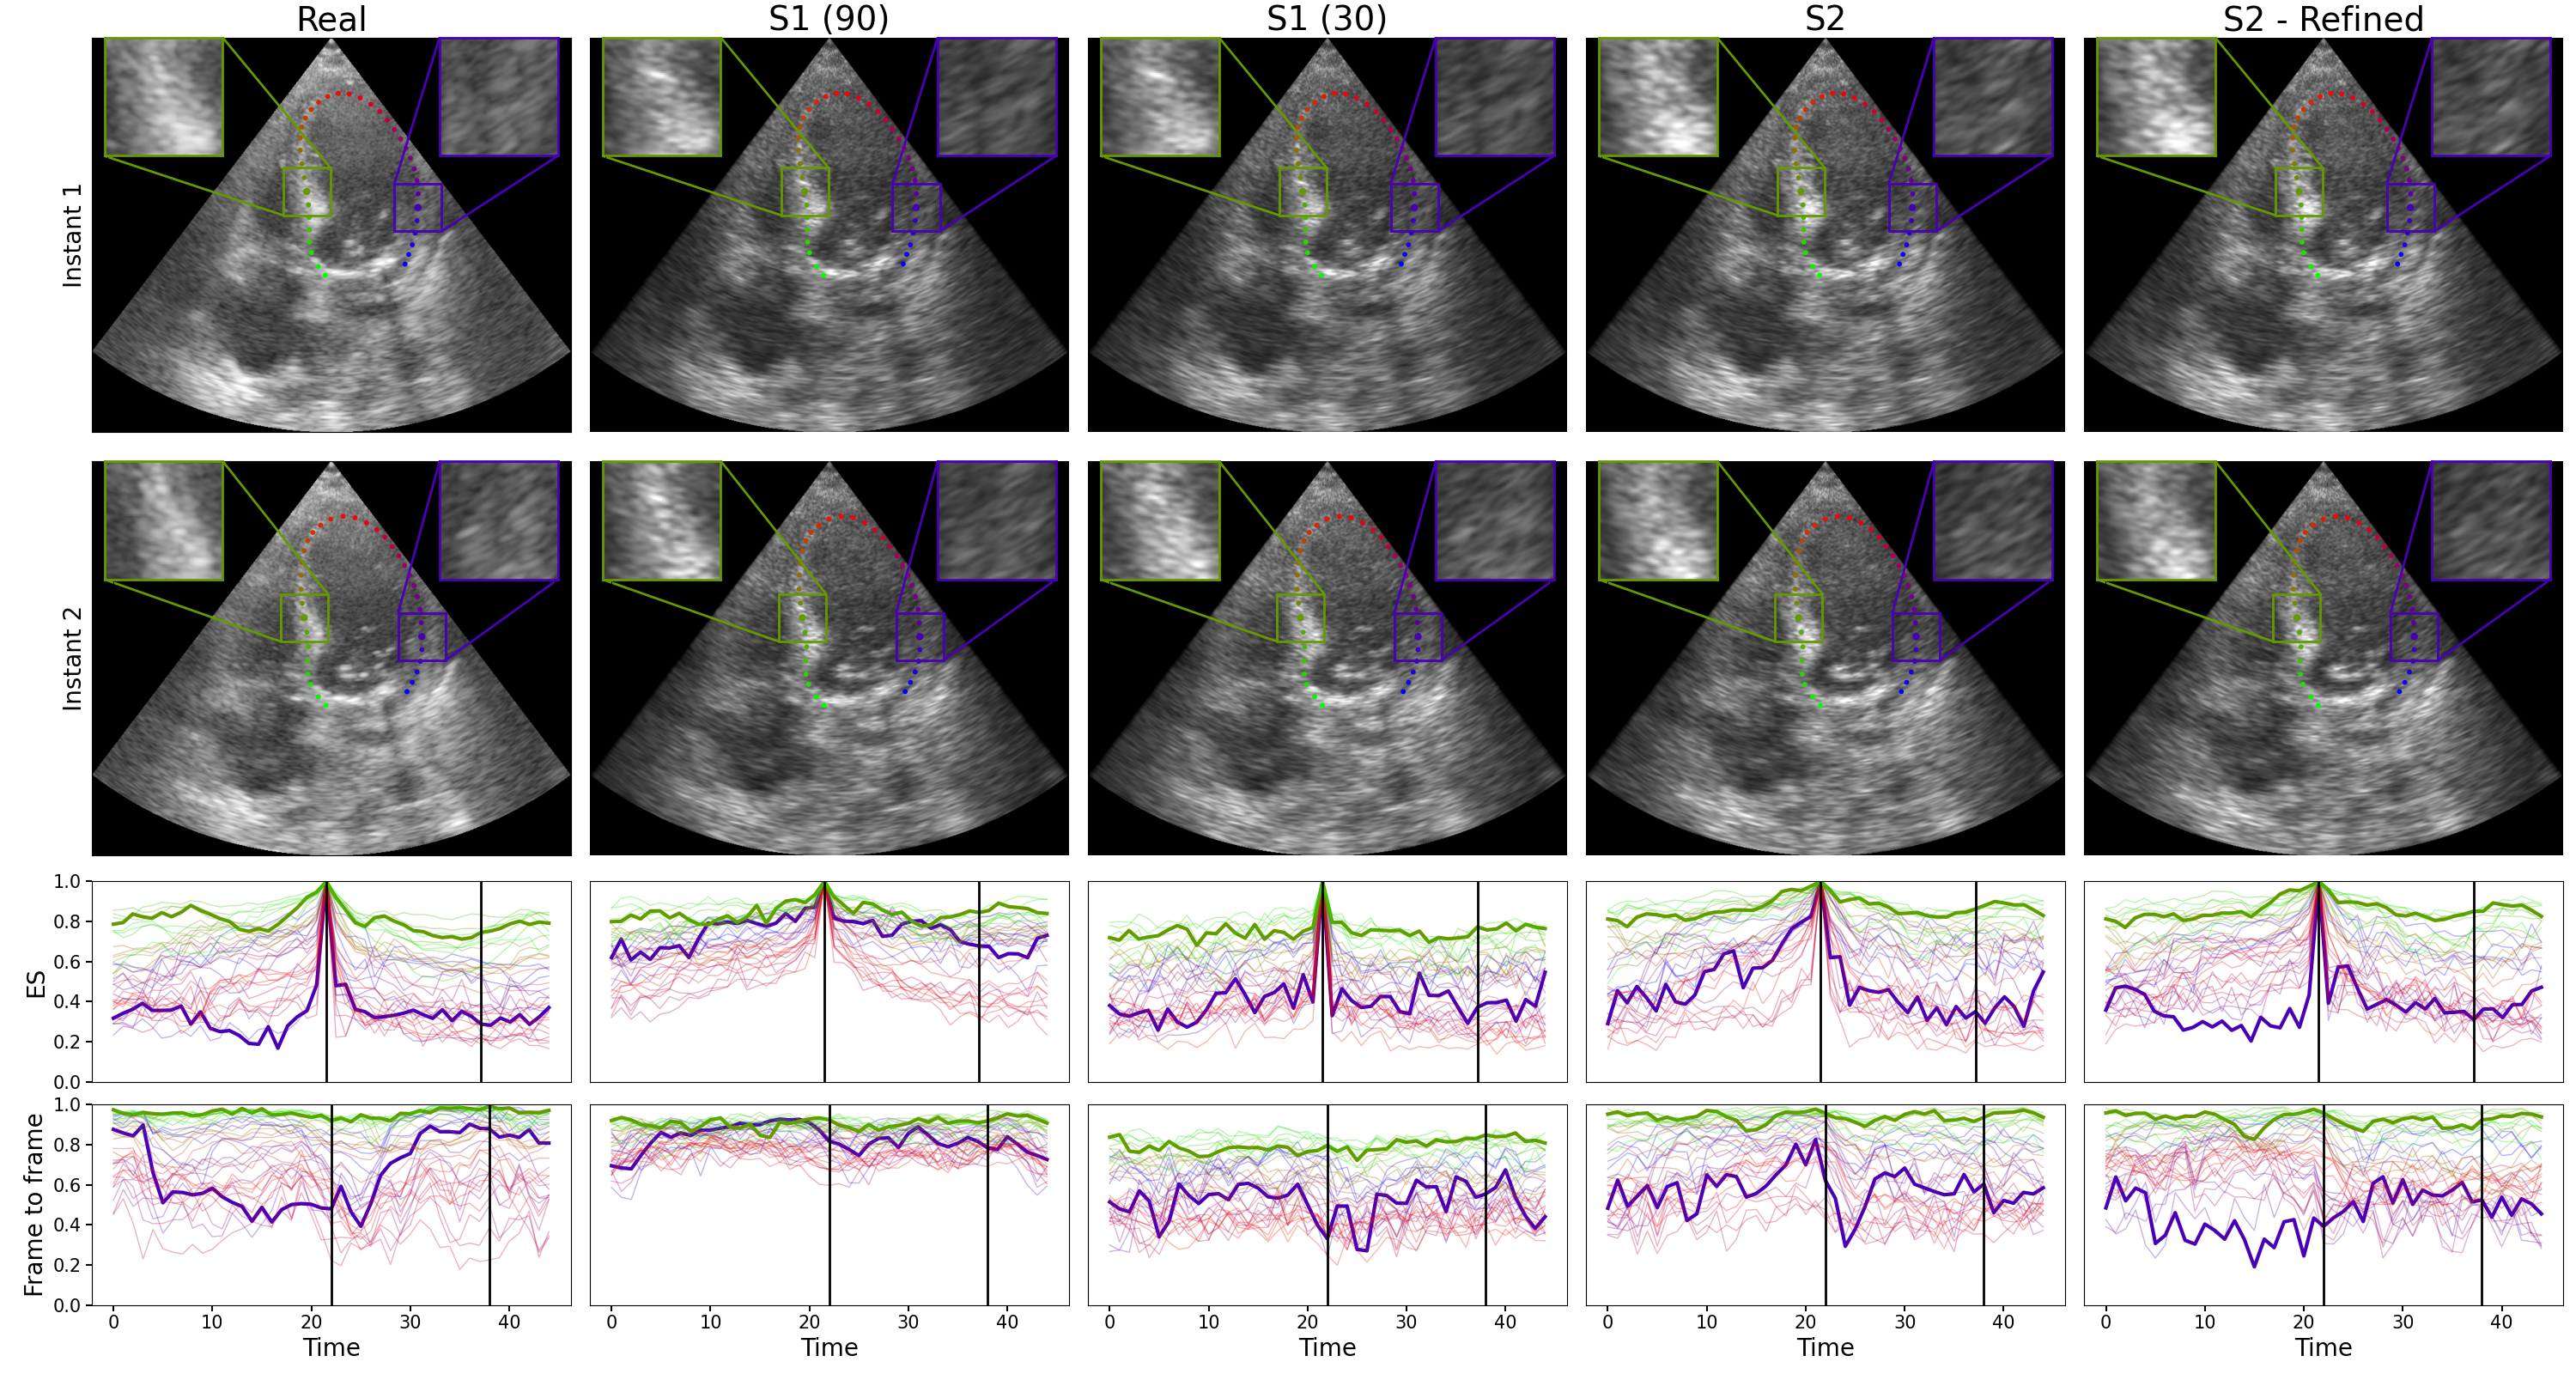

Figure 3: Example of two distinct frames from real and simulated sequences. Correlation curves with ES reference and frame-to-frame reference are shown in the last two rows for the 36 center line points. The highlighted curves represent the points in the zoom regions of the images. Black vertical lines indicate the first and second instants.

We conduct an evaluation on a subset of 98 patients from the CAMUS dataset [7]. For each patient, a full cardiac cycle of the four-chamber view was manually segmented. This segmentation was used to produce the reference motion mesh. We simulated according to the first strategy (S1) with different values of pp as well as strategies 2 with and without refinement; S2, S2-Refined. We report the mean absolute error (MAE) between the curves from the real video and simulated video averaged across all 98 sequences. We report the MAE for correlation curves with the reference frame set to ES (as is used for strategy 2). We also compare frame-to-frame correlation curves where the reference window is taken in the previous frame, as some optical flow methods work in image pairs rather than full videos. We also compute the average correlation across the sequence as an indicator of the global correlation level and how it compares to real data.

Results are shown in Table I. The best results are obtained with strategy S2 - Refined, which outperforms S2 and the best version of strategy 1: S1-30. The results show that decreasing the value of pp decreases the MAE and average correlation. However, reaching S1-30, the frame-to-frame MAE increases, and the average correlation level is lower than the real data, indicating the correlation is too low. Qualitative results in Fig. 3 confirm the S1-30 simulation has too little correlation. It also shows that both S1-90 and S1-30 have very constant correlation throughout the video, but at different levels. On the other hand, both versions of strategy 2 have lower correlation but preserve high correlation areas by having more correlation variability both in time and space (across different curves).